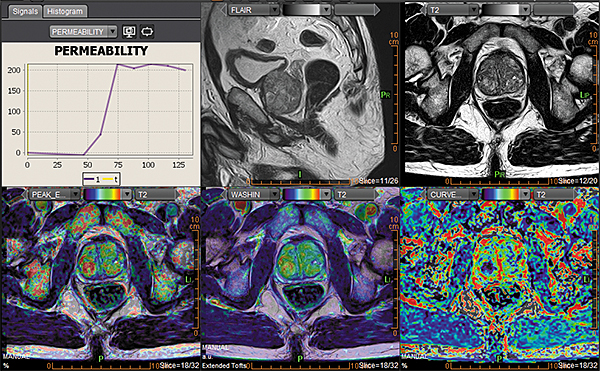

Додаток Prostate Streamlined.

Спеціальні програми Olea SphereTM для аналізу передміхурової залози включають в себе розширені можливості для оцінки дифузії та якісної оцінки перфузії. Також пропонують ефективний мультипараметричний аналіз усіх доступних послідовностей для візуалізації простати. В додатках реалізовано аналіз кінетики та кількісних даних на основі надійних математичних моделей. Програми передміхурової залози включають звіт PI-RADS® 2 для покращення виявлення, характеристики та вірогідності встановлення діагнозу раку простати. Цей програмний пакет стандартизує виклад протоколів опису, а також вказує рівень підозри або ризик виникнення клінічно значущих пухлин.

Додаток MR Prostate

Додаток MR Prostate інтегровано до розширеної візуалізації Vitrea. Він забезпечує виявлення, характеристику та стадіювання ураження.

Забезпечує миттєву комплексну оцінку ураження та високоякісну оцінку дифузії

Дає змістовну звітність, включаючи локалізацію та об’єм ураження

Надає рекомендації PI-RADS V2 щодо стандартизації термінології і протоколу опису, а також уточнює ризик клінічно значущих пухлин